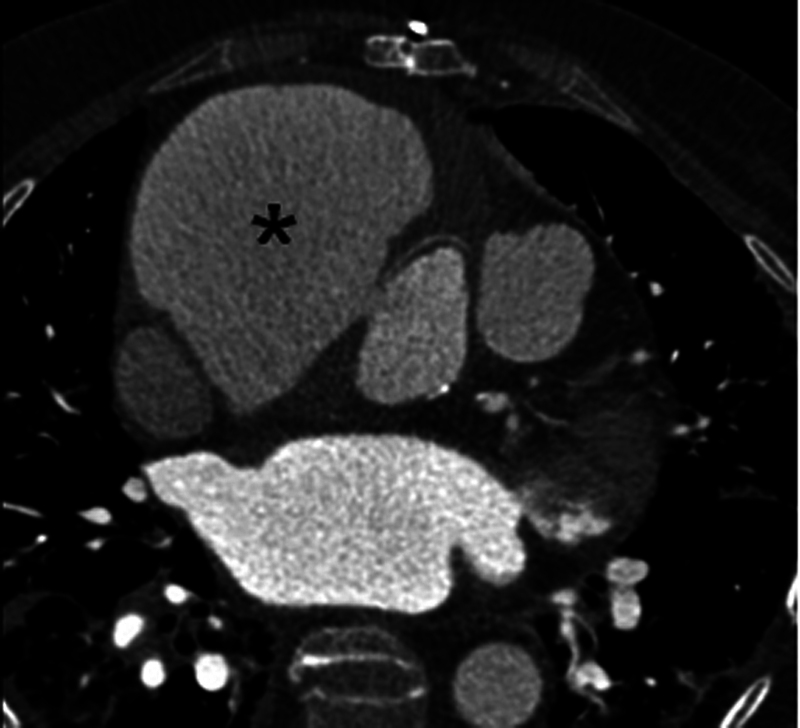

Aortic pseudoaneurysm occurs in 10 to 24% of patients after acute type A aortic dissection repair. We report the case of a 72-year-old female who developed an intraoperative iatrogenic ascending aortic dissection following mitral valve repair. A giant ascending aortic pseudoaneurysm was detected on follow-up imaging. This case emphasizes the importance of close radiological surveillance following acute aortic dissection repair.

Abstract Image